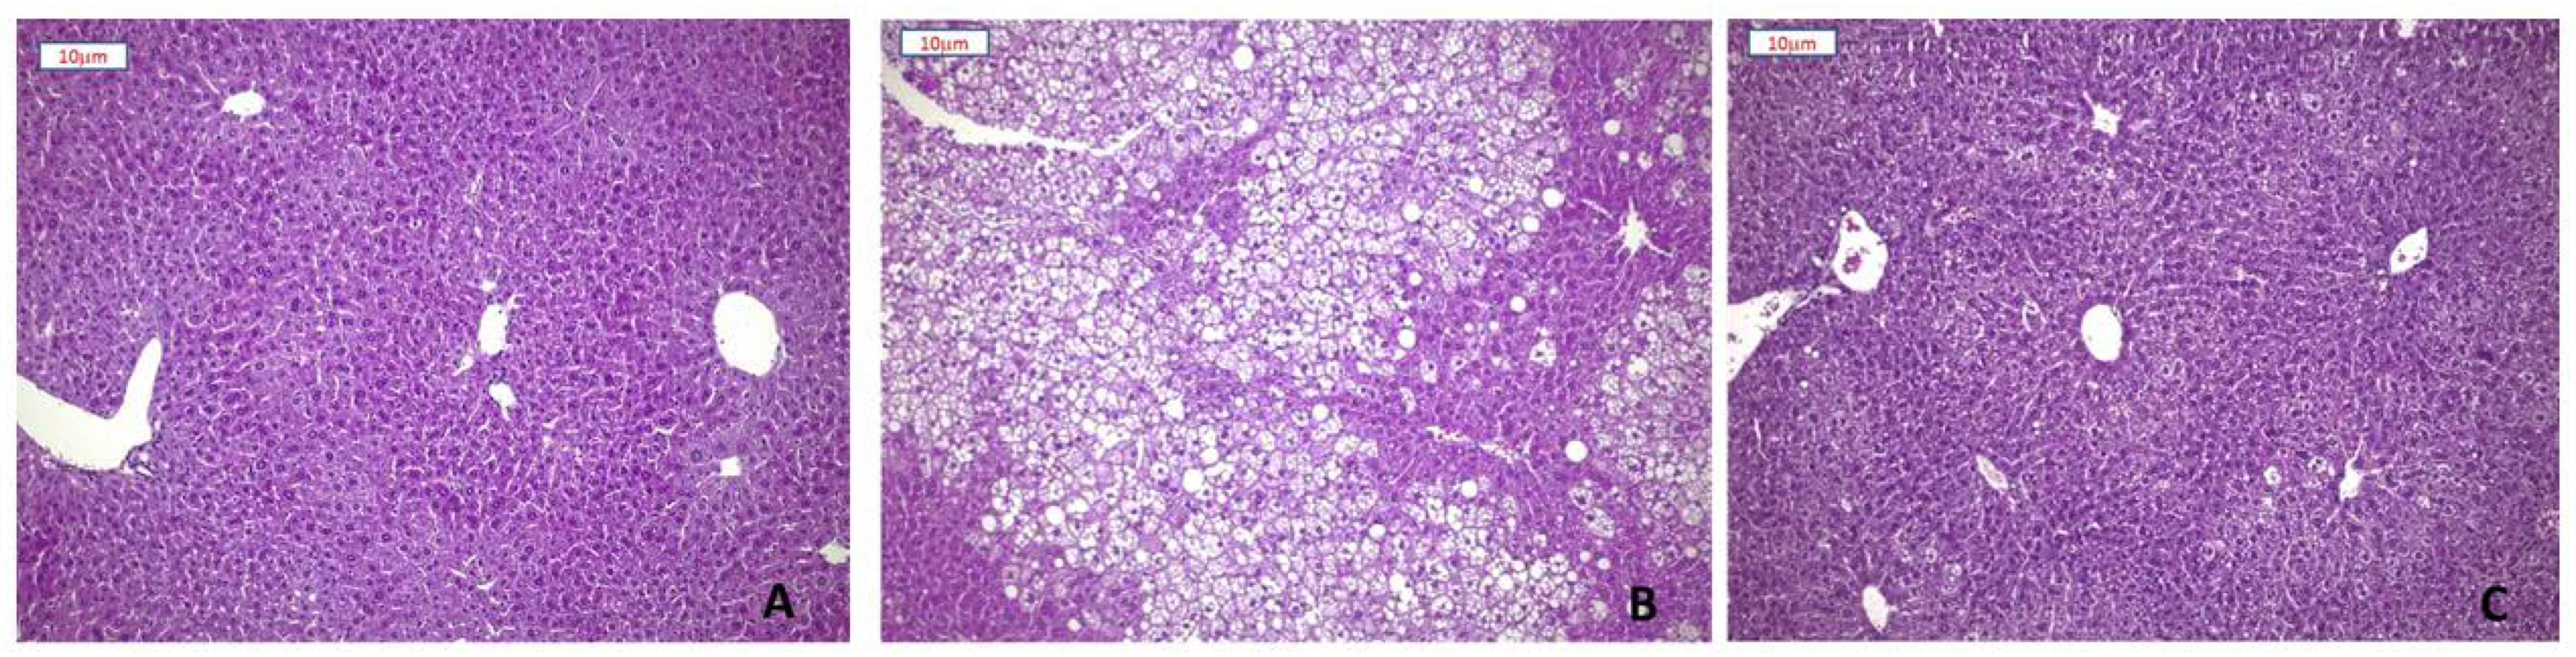

3.2. Effect of Plant Extracts on Steatosis Development of HFD Mice